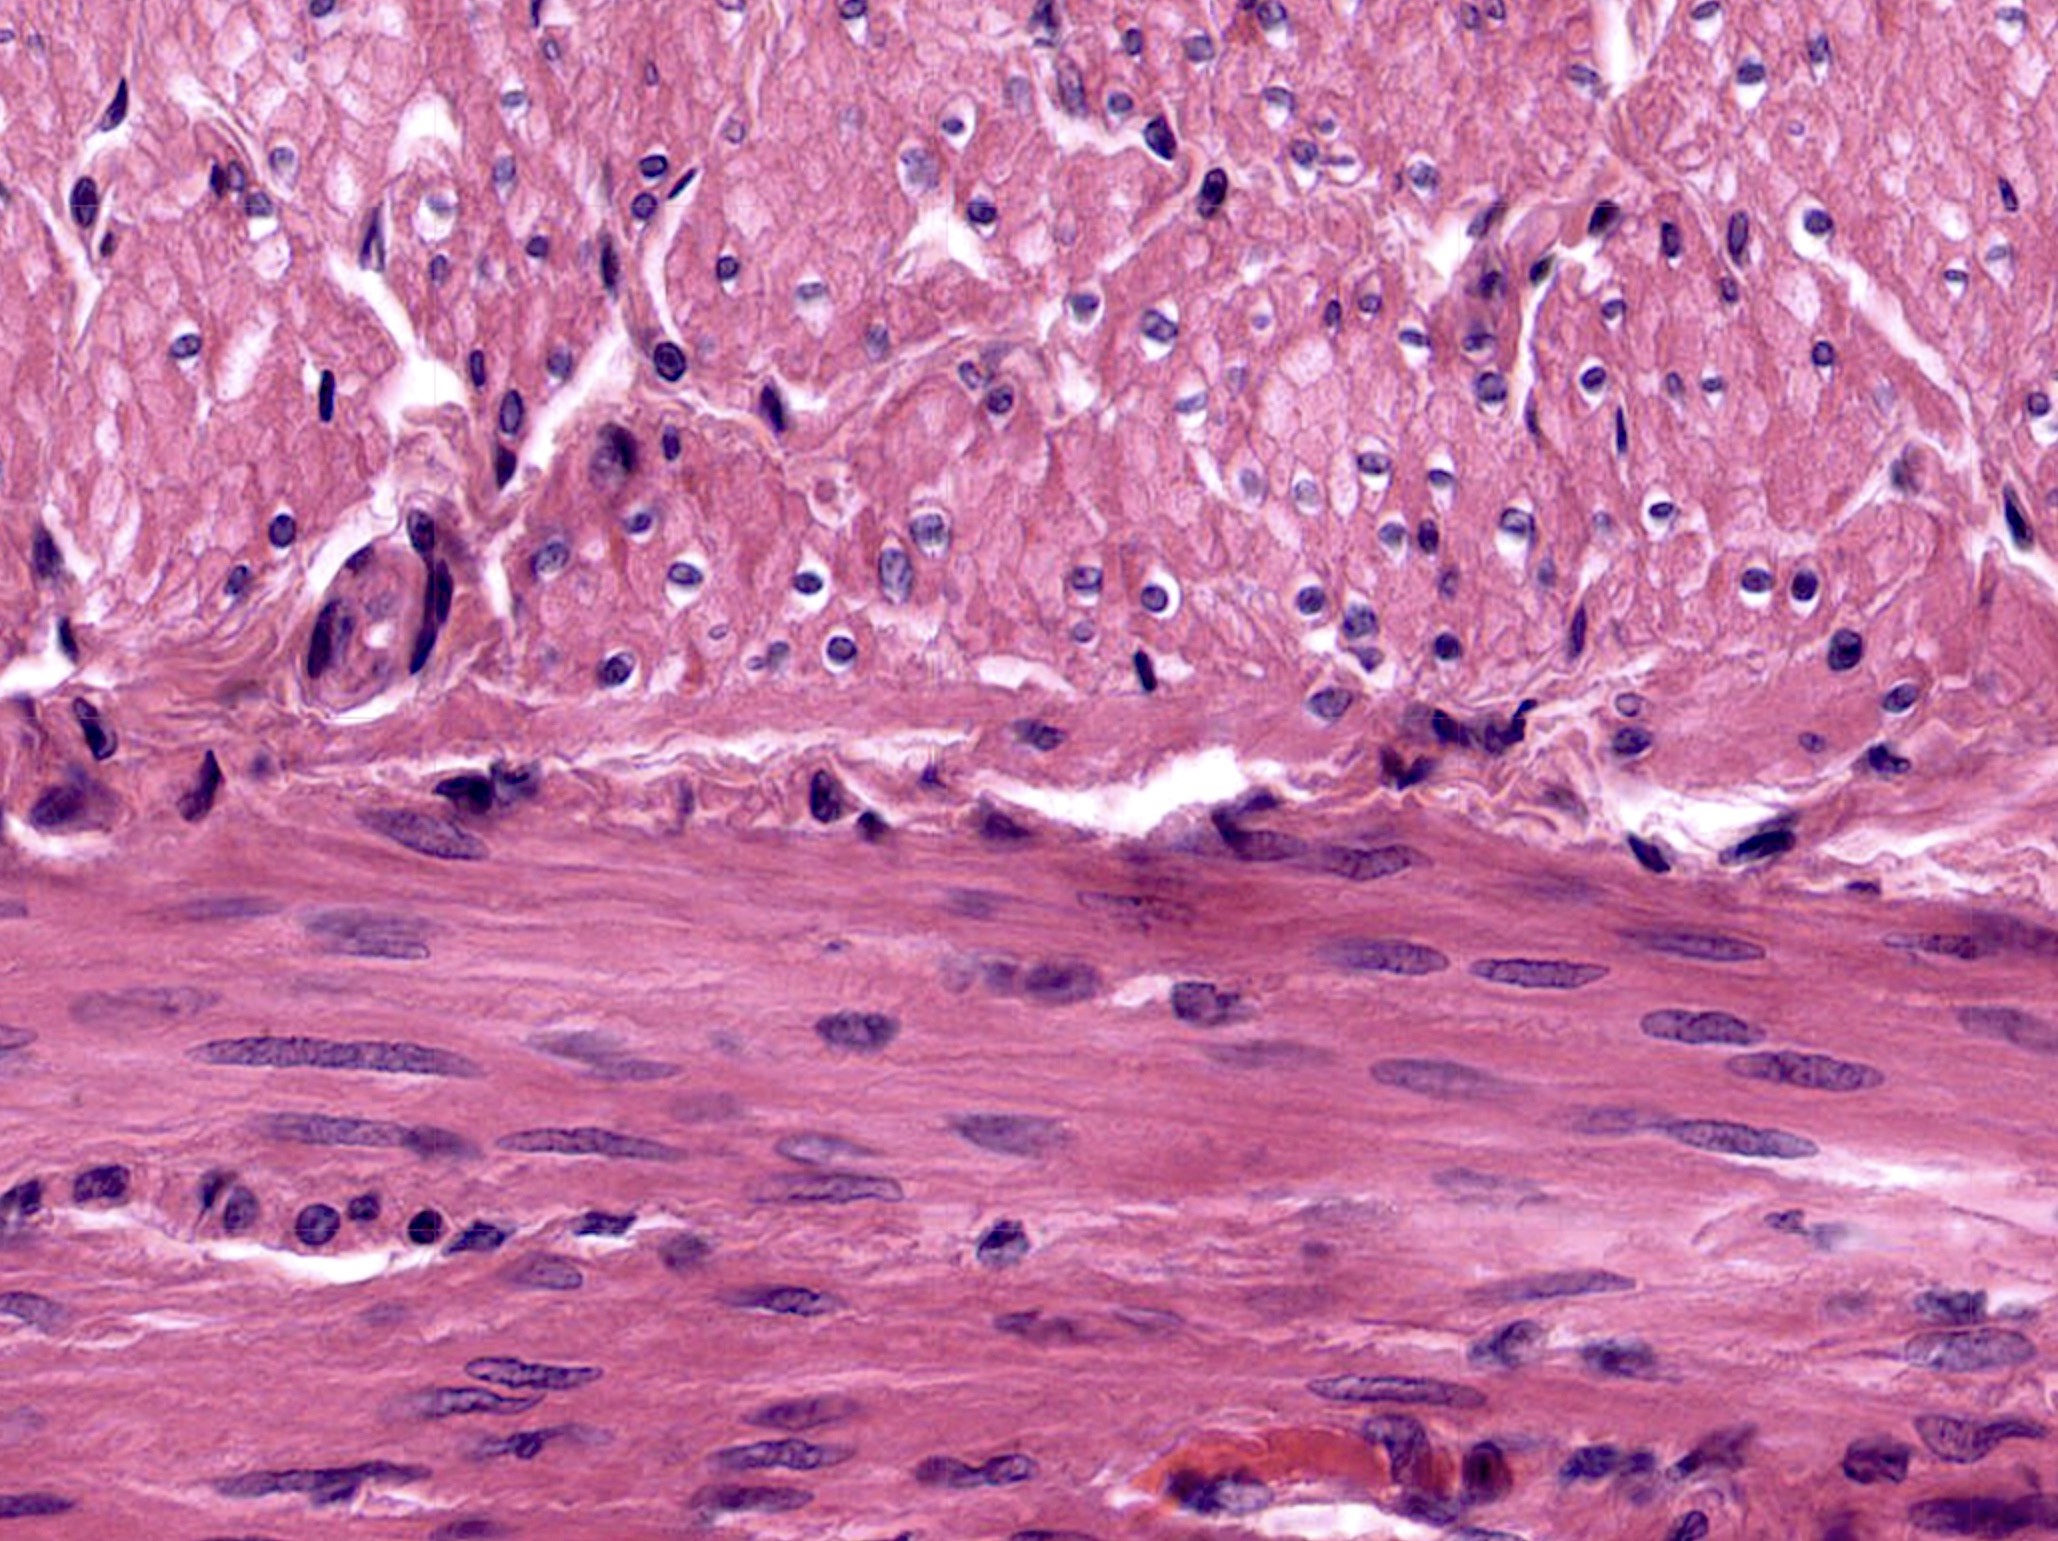

Smooth muscle cells (leiomyocytes) are elongated, fusiform (spindle-shaped) cells, tapering at each end. Size varies by location — vascular smooth muscle ~20 µm, uterine smooth muscle during pregnancy up to 500 µm.

2. Nucleus

Single, centrally placed elongated oval nucleus. In contracted cells, the nucleus appears corkscrew/cigar-shaped due to cellular contraction. This is a key distinguishing feature from skeletal muscle (peripheral nuclei) and cardiac muscle (central but 1–2 nuclei with intercalated discs).

Smooth muscle cells are arranged in sheets or fascicles. In a longitudinal section, cells appear as elongated spindles staggered so the thickest part of one cell is adjacent to the tapered end of another — maximising packing efficiency. In cross-section, cells of varying diameters appear as irregularly sized circles (some cut through the widest part, some through the tapering ends).

Distinguishing Features on Slide

- Spindle-shaped cells with central nuclei — NO striations

- In cross-section: circular profiles of varying sizes

- Corkscrew nuclei in contracted cells

- Fine connective tissue between cells

- Capillaries visible between bundles